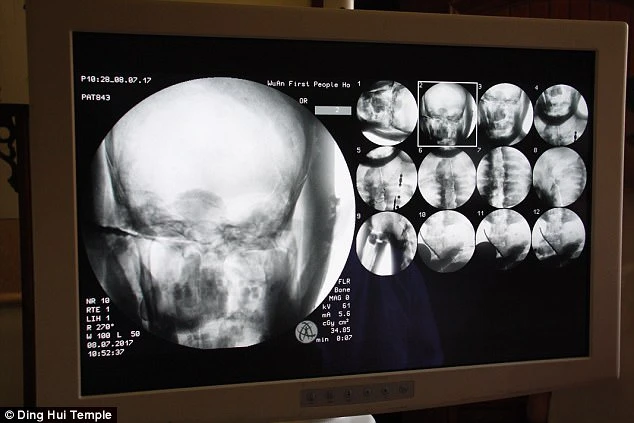

Sự kiện gây chấn động diễn ra vào ngày 8 tháng 7 năm 2017, khi các nhà khoa học tiến hành chụp CT để kiểm tra bên trong “bức tượng” này trước sự chứng kiến của giới truyền thông và đông đảo người dân. Kết quả hình ảnh quét được đã khiến tất cả những người có mặt phải bàng hoàng. Các bác sĩ xác nhận rằng bên dưới lớp mạ vàng, nhà sư Ci Xian vẫn giữ được bộ xương nguyên vẹn cùng một bộ não hoàn chỉnh.

Kết quả hình ảnh từ máy quét đã khiến toàn bộ giới khoa học và những người chứng kiến phải kinh ngạc đến mức sững sờ. Các bác sĩ xác nhận rằng nhà sư Ci Xian vẫn còn giữ được một bộ xương hoàn chỉnh cùng một bộ não nguyên vẹn.

Bác sĩ Wu Yongqing, người trực tiếp tham gia buổi kiểm tra cho biết xương của ngài khỏe mạnh và rõ ràng như một người bình thường. Từ xương hàm trên, răng, xương sườn, xương sống cho đến tất cả các khớp đều vẫn còn nguyên vẹn một cách khó tin. Sự tồn tại hoàn hảo của thi hài sau hơn 1.000 năm đã chứng minh kỹ thuật ướp xác đỉnh cao thời bấy giờ, tạo nên một hiện tượng chấn động khiến cả thế giới phải chú ý.

Những hình ảnh có được sau khi chụp CT